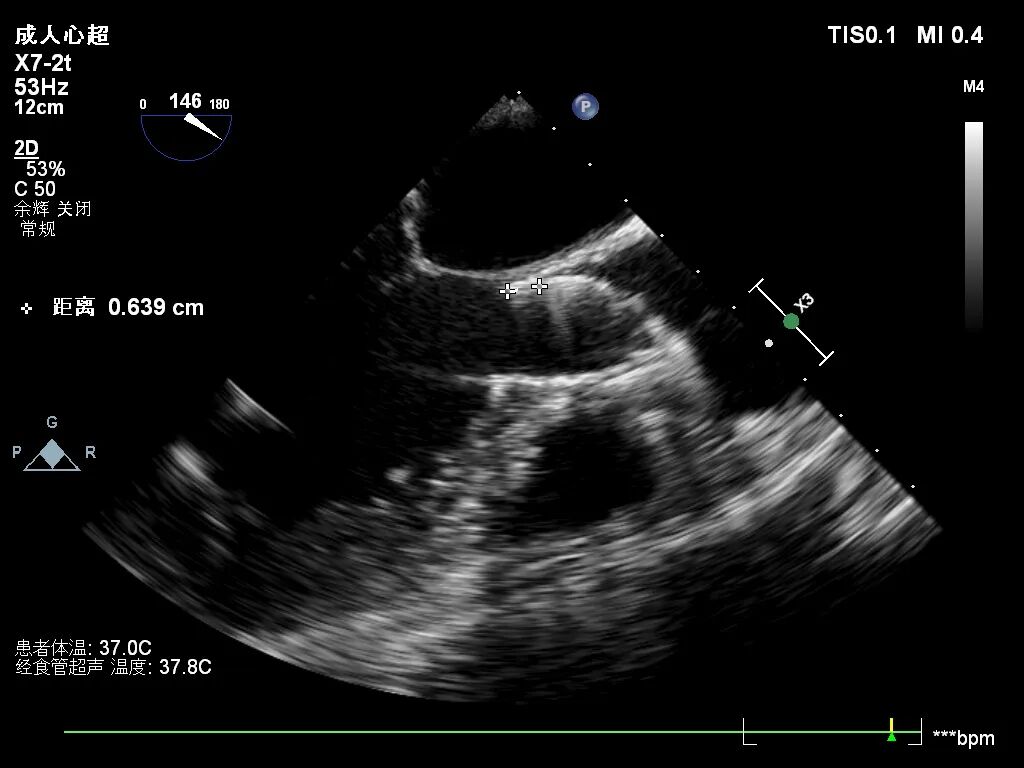

超声看位置合适,无反流

超声看左冠窦侧6mm左右

超声看完全释放下滑至7mm